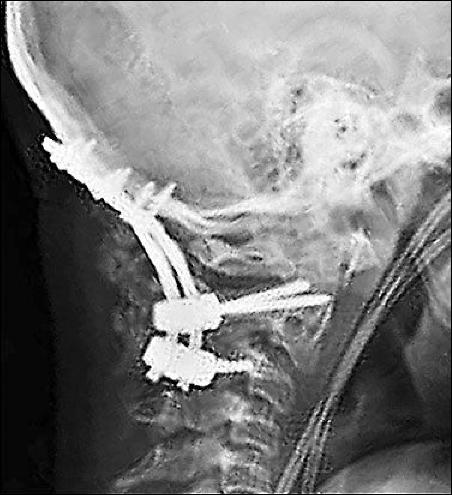

鈦合金的鋼釘被植入了頸椎

最后再強(qiáng)調(diào)一句,如果你頸椎痛的已經(jīng)不行了,千萬別做手術(shù),我可以負(fù)責(zé)任地說,做一個(gè)完蛋一個(gè)。我曾經(jīng)見過一個(gè)30多歲的公司老總,胖的不行,脖子里打了好幾根鈦合金的鋼釘,現(xiàn)在基本上是“廢人”一個(gè)了。當(dāng)我給他講完這頸椎病的事,他后悔不已。本來很簡單的事,醫(yī)生為了掙錢,就給他打了鋼釘,把他變成了“廢人“。但是,當(dāng)有人告訴你,刮痧可以治頸椎病時(shí),你會(huì)相信嗎?很少有人會(huì)信,為什么呢?因?yàn)榭粗蝗绱蜾撫攣淼挠屑夹g(shù)含量。所以,人就是這么無知,被忽悠了,最后搞的是人財(cái)兩空。